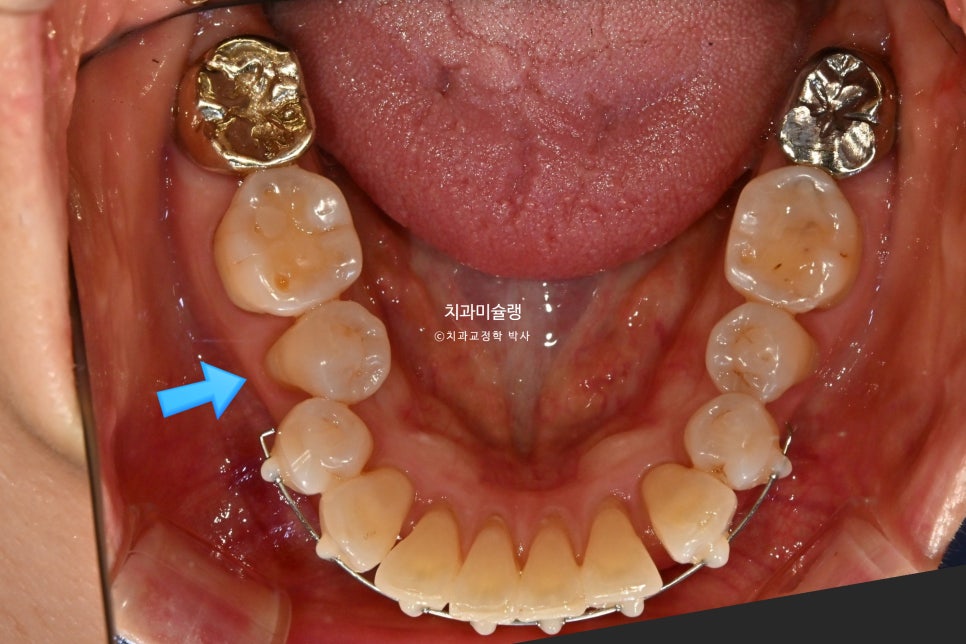

아래는 첫번째 작은어금니까지 배열이 되고 나니 두번째 작은어금니가 안으로 쓰러진 부분이 더 눈에 띄게되었습니다.

그래서 해당부분만 장치를 더 연장하는것으로 환자분을 설득했습니다.

작은어금니까지 배열이 가지런해졌습니다.

통상 앞니 부분교정에는 최장 6개월이 소요되지만, 부분교정용 장치로 어금니까지 욕심을 내어 기간이 조금 더 걸렸습니다.

어금니 교합은 우측은 1급, 좌측은 2급 교합 관계를 보이나, 물샐틈 없이 잘 물립니다.

치간삭제를 통해 블랙트라이앵글은 많이 줄었으며

앞니 뻗침도 소량 개선되었습니다.

고정식 유지장치까지 들어간 모습입니다.